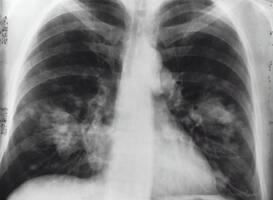

Het aantal mensen met tuberculose (tbc) in Nederland is in 2021 iets toegenomen. In 2021 waren er 680 tbc-patiënten in Nederland. Dit is 9 procent meer dan in 2020 (622 patiënten). Bij 296 patiënten bevond de tuberculose zich buiten de longen. Er waren 384 patiënten met tbc in de longen. Hiervan hadden 141 open tuberculose, de meest besmettelijke vorm. Dit meldt het RIVM.

Tuberculose is een infectieziekte die wordt veroorzaakt door een bacterie. De ziekte is meldingsplichtig. Dit betekent dat artsen de ziekte moeten melden aan de GGDt. De GGD meldt dit vervolgens aan het RIVM. Tuberculose kan besmettelijk zijn, bijvoorbeeld als de ziekte in de longen zit.